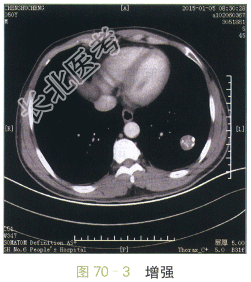

影像学资料如图70-1~图70-4所示。

图70-1~图70-4胸部CT平扫与增强:左肺下叶类圆形肿块,边缘光滑,瘤灶内斑点状钙化,呈爆米花样改变,增强扫描未见明显强化

读片分析:CT表现:左肺下叶类圆形肿块,直径约2.7cm,边缘光滑清楚,瘤灶内见多发的小斑片状钙化,呈爆米花样改变,增强扫描未见明显强化。